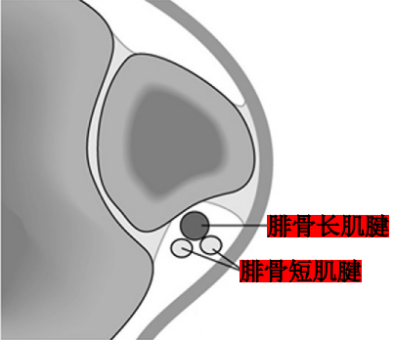

Raikin等学者提出将腓骨沟内腱鞘内半脱位不伴有腓骨上支持带损伤划为腓骨脱位的亚系。这些腱鞘内半脱位共有两型:

A型:腓骨肌腱无撕裂,肌腱暂时换位;

B型:腓骨短肌存在纵向撕裂,腓骨长肌腱自撕裂处半脱位。